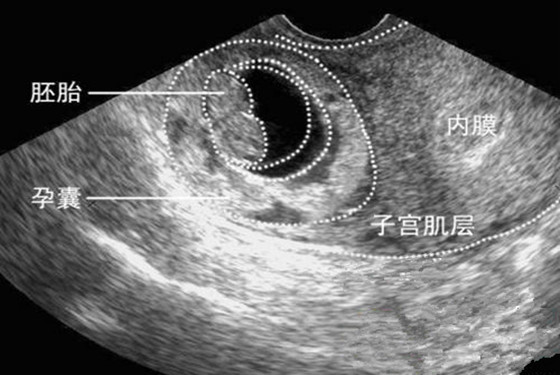

2、孕囊形状:早期孕囊形状圆圆的,怀女宝的可能性比较大;